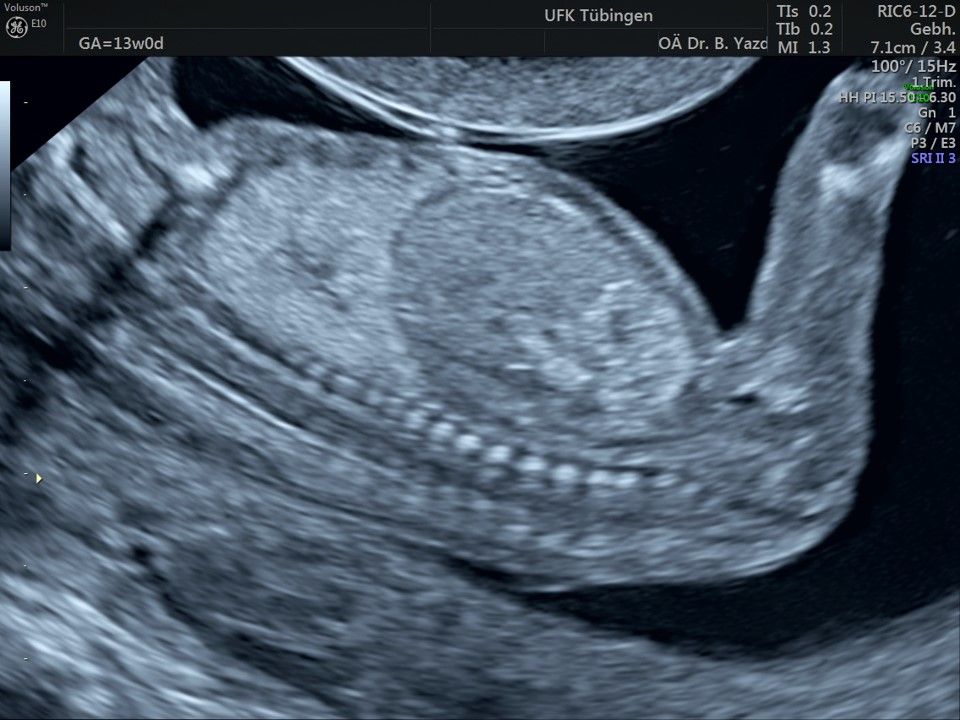

Im Rahmen des Ersttrimester-Screenings untersuchen wir die Organe des Feten mittels Ultraschall. Dabei machen wir auch gerne ein Bild für Sie.

Obwohl der Fet zu diesem Zeitpunkt erst zwischen 5 und 8cm groß ist, lassen sich bereits etwa die Hälfte aller schwerwiegenden Fehlbildungen erkennen bzw. ausschließen. Sollten wir eine Auffälligkeit sehen, werden wir mit Ihnen den Befund und das weitere Vorgehen ausführlich besprechen.

Die eigentliche Organuntersuchung findet um die 20.SSW (zweites Screening) statt. Das Ersttrimester-Screening und das zweite Screening sind sich ergänzende Untersuchungen und ersetzen sich gegenseitig nicht.